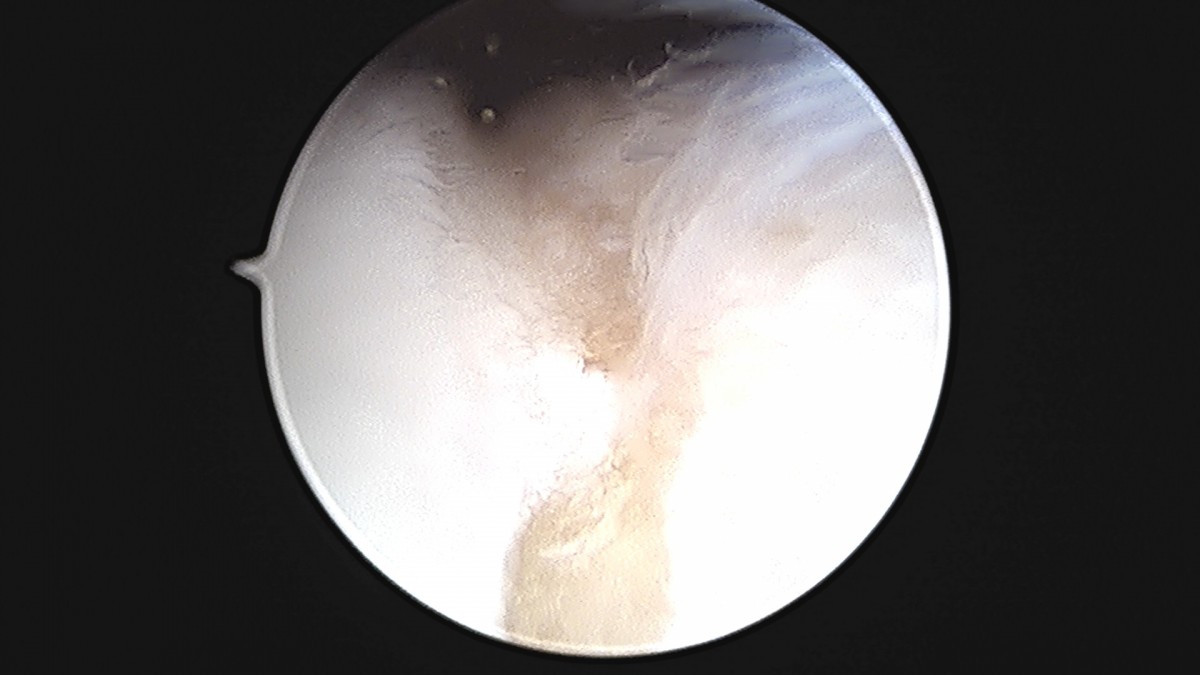

정지영원장님 발목 변연절제술 권공O 환자

작성자 최고관리자 댓글 0건 조회 743회 작성일 25-09-16 17:04